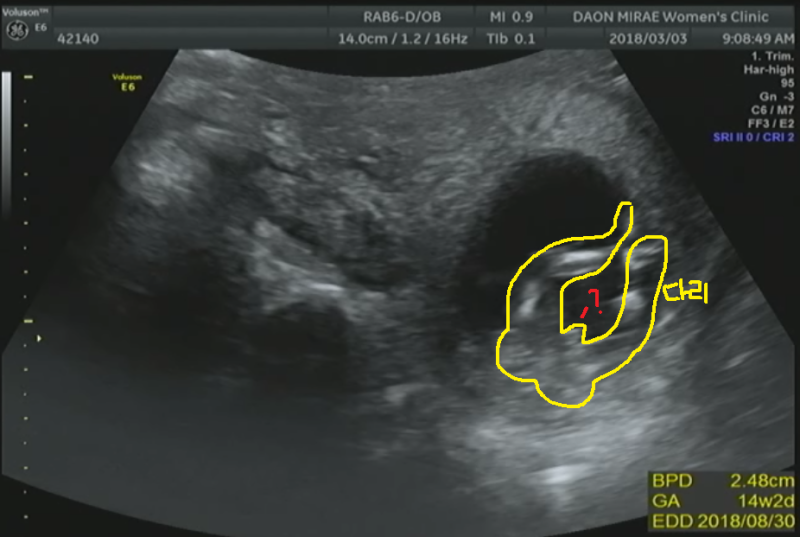

임신 13주의 축복이 예비 엄마 셀리의 일상 임신 13주를 맞이하여 1차 기형아 검사를 해왔습니다.

아기의 목 주위 투명대를 측정하여 태아의 기형 여부를 조사하는 검사였습니다.

다행히 축복의 목둘레는 정상 범위였습니다.

그리고 초기 정밀 초음파를 통해 처음으로 입체 초음파로 축복의 모습을 보았습니다.